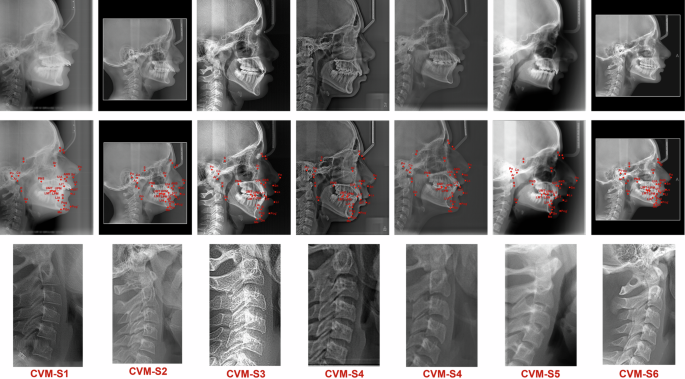

The development of automated landmark detection systems has been hindered by a lack of reliable datasets. In an effort to address this gap, we present a novel dataset of lateral cephalometric radiographs (LCRs) annotated with 29 of the most commonly used anatomical landmarks, including 15 skeletal, 8 dental, and 6 soft-tissue landmarks. Our dataset, which comprises 1000 radiographs obtained from 7 different imaging devices with varying resolutions, is the most diverse and comprehensive cephalometric dataset to date. In addition to the extensive annotation of landmarks, our team of clinical experts also labelled the cervical vertebral maturation (CVM) stage of each radiograph, creating the first standard resource for CVM classification. A representative sample of annotated cephalograms from each imaging device, along with their respective CVM stages, is illustrated in Fig. 7. Offering a diverse range of images acquired from different X-ray machines and providing a comprehensive set of annotations, our dataset has the potential to greatly improve the accuracy and reliability of automated cephalometric landmark detection systems, ultimately leading to more informed orthodontic treatment decisions.